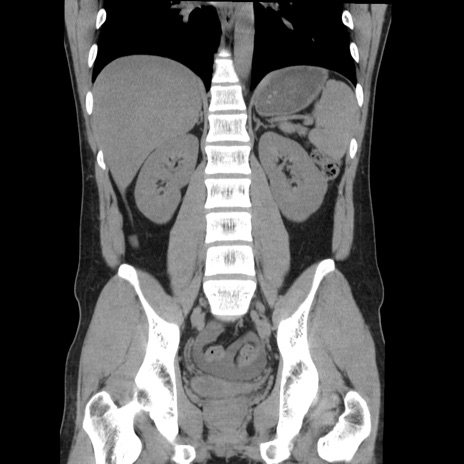

症例36(冠状断像)

【症例】20歳代 男性

【主訴】心窩部痛

【現病歴】今朝より上腹部痛あり。一旦軽快していたが再度出現したため救急要請。昨日夕に白身の魚を含む刺身を食べた。

【身体所見】BP 136/89mmHg、HR 74/min、BT 37.0℃、腹部:膨満、軟、心窩部に圧痛あり。反跳痛なし、筋性防御なし、腸雑音やや亢進あり。

【データ】WBC 17700、CRP 0.48

横断像